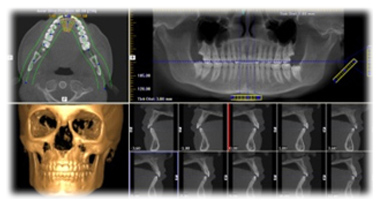

研讨主题:《All-on-4即刻种植牙技术应用》 徐世同教授

All-on-4是欧美最新的口腔种植牙技术之一,通俗的来讲,它是将全口无牙的病人,通过植入较少的种植牙(上下各植入4颗种植体)来达到重建全口牙齿的目的一个简单而有效的解决方案。

一般来说,所有的全口、半口无牙颌病人都All-on-4种植牙修复的适应人群,特别是对于想做种植牙修复但是估量不足,又不想通过植骨来完成种植牙修复的患者来说,All-on-4 种植牙修复无疑是一个简单而有效的解决方案。

即刻种植·即刻负重——All-on-4结合倾斜植体和即刻负重等外科与修复方面的创新, 实现在手术当日即刻负重,只需4个植体就可做半口固定义齿修复,1小时完成整个种植过程。

无需植骨·无需戴牙——过去全口或半口等牙列缺失的患者往往要接受植骨手术,承担 多次手术和较长的愈合期,All-on-4技术真正做到即使在骨量严重萎缩的情况下,也可利用斜行植体等技术,避免植骨手术。

适应面广·效果稳定——所有全口、半口无牙颌病人都是All-on-4的适应人群,即使在骨量最小的情况下也可实现稳定性。

存活率高·使用持久——临床研究结果显示, All-on-4显示出良好的临床效果,成功率超过98%,一次种植可保持40年以上,融合德、美、瑞等国际顶尖种植系统,更具有极强固位,稳定耐磨抗腐蚀。

技术特色:通过植入较少的种植牙(上下各植入4颗种植体)来达到重建全口牙齿的目的。1小时完成整个种植过程。即使在骨量严重萎缩的情况下,也可利用斜 行植体等技术,避免植骨手术。

适应症状:全口牙缺失、半口牙颌缺失、种植骨量不足